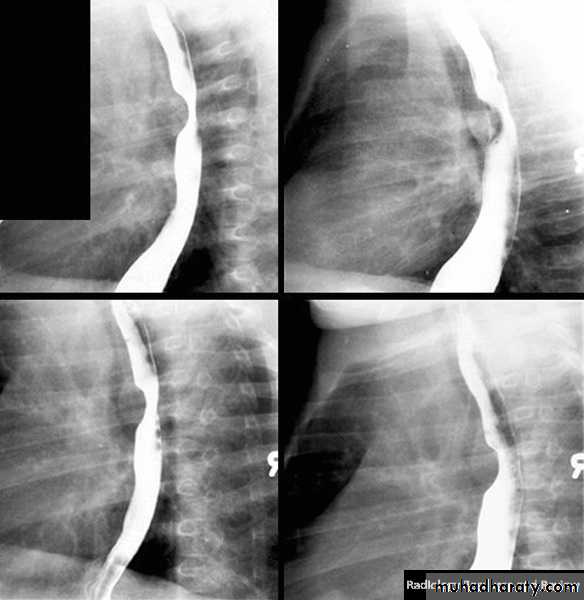

• Ulcer: benign vs. malignant/ size

Diverticulum

Types Causes Specific TypeUlcer

Types CausesContour changes

Causes